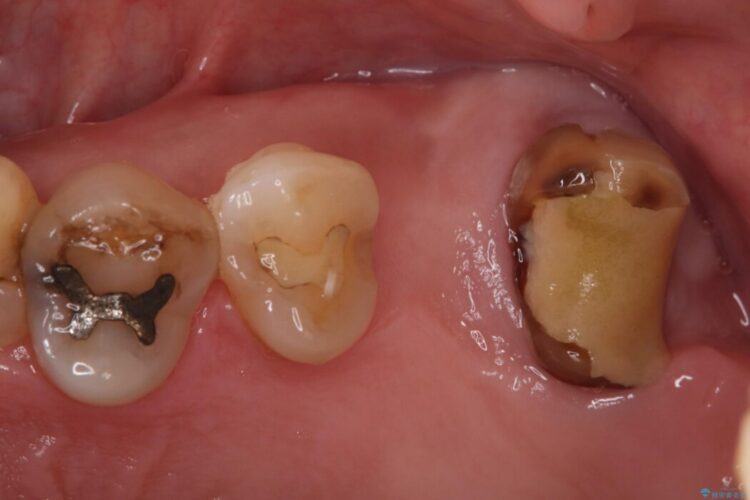

精密検査の結果、治療を中断していた左上7番は重度の虫歯や歯周組織の崩壊により保存が難しい状態でした。

6番も歯を失ってから時間が経っていたため、奥歯でしっかりと噛むことができない状態でした。